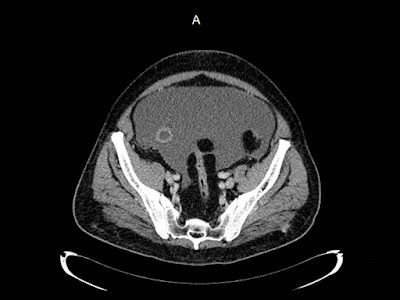

Paciente de 72 años con antecedente de tuberculosis genitourinaria hace 40 años.